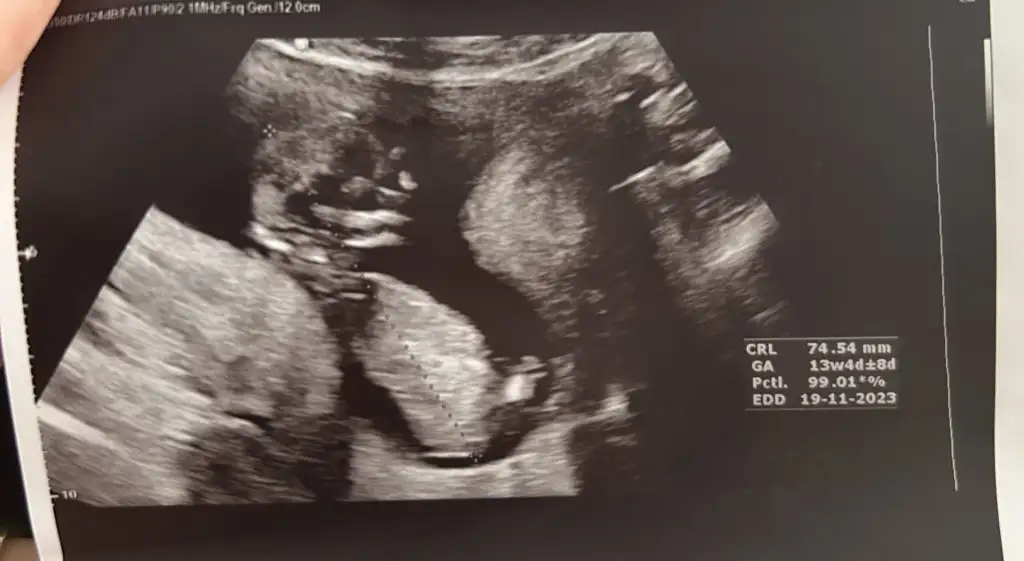

senle günlerimiz aynı bana da geçen hafta büyük ihtimal erkek dedi haftaya tekrar gideceğim senin ki gibi sonradan kız demesi eşimin beklediği sürprizBugün doktor kontrolümüz vardı. Geçen hafta erkek gibi duruyordu bu hafta kesin kız olduğunu gördükkkk.Ultrason fotoğraflarından da erkek çıkıyordu nub falan bende çürüdü yani.

maşallah hareketli bi bebiş geliyor demekkiKızlar dünyanın en saçma sorusu olabilir ama biz doktordan çıktık gene azcık önden gidiyoruz aç karnına girdim ultrasona bebek inanılmaz zıplıyordu nasıl yani hareket etmek gibi değilde sıçramak hıçkırmak gibi 12.haftada normal mi bu ya doktorda yandınız siz ilerde diyor